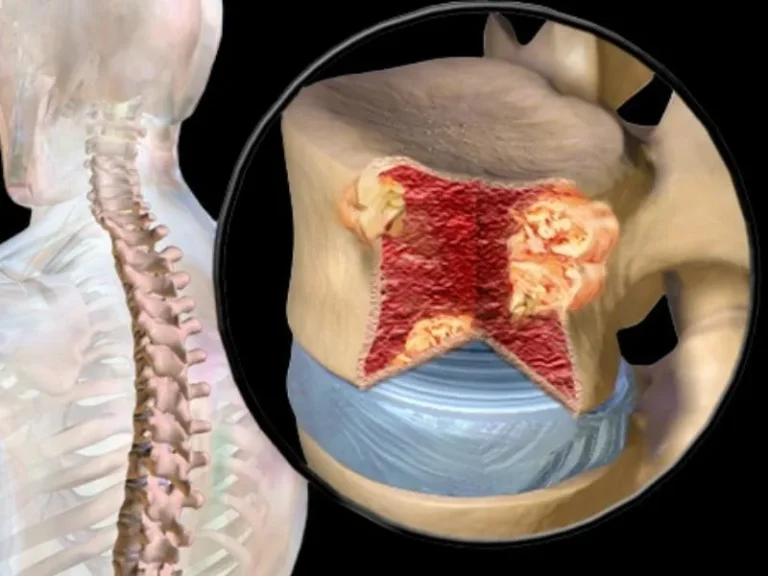

หมอนรองกระดูก“เสื่อม” เกิดจากสาเหตุหลักๆคือ1.เกิดจากใช้งานในชีวิตประจำวัน2.อายุที่มากขึ้น

ปัจจุบันพบในผู้ป่วยอายุที่น้อยมากขึ้นเนื่องจากการใช้ชีวิตประจำวันและพฤติกรรม...

วันนี้เราจะมาทำความรู้จักกับ 1 โรค ที่พบได้บ่อยมากขึ้นและเป็นอันตรายกว่า โรคกระดูกสันหลังทับเส้นประสาทนั้นคือ “โรคเนื้องอกในไขสันหลัง”

โรคเนื้องอกในไขสันหลัง...